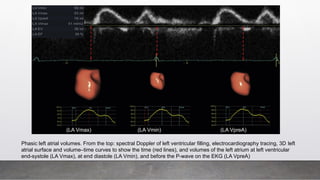

Phasic LA Volumes Calculation:

○ Maximal LA Volume: Just before mitral valve opening

○ LA PreA Volume: At onset of P wave on ECG

○ Minimal LA Volume: At end-diastole (before mitral valve closure)

Phasic left atrial volumes. From the top: spectral Doppler of left ventricular filling, electrocardiography tracing, 3D left

atrial surface and volume–time curves to show the time (red lines), and volumes of the left atrium at left ventricular

end-systole (LA Vmax), at end diastole (LA Vmin), and before the P-wave on the EKG (LA VpreA)